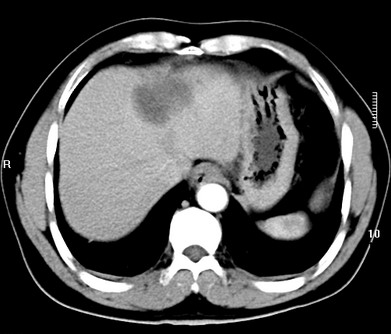

标题: CT19720:肝右叶血管瘤。肝左叶内侧段病灶考虑什么? [打印本页]

标题: CT19720:肝右叶血管瘤。肝左叶内侧段病灶考虑什么?

男,48岁,肝区不适月余,伴隐痛。

支持右叶血管瘤,左叶病灶考虑肝腺瘤。

1)不排除肝左叶肝癌。2)肝右叶血管瘤。

肝左叶炎性病变,肝癌待排。2)肝右叶血管瘤。

1.肝右叶血管瘤;2.肝左叶炎性假瘤?肝癌?建议穿刺活检.

右叶病灶典型,左叶病变慢性炎块

1、肝右叶血管瘤(典型)。

2、肝左叶病灶,强化不明显,疑炎性假瘤,建议结合临床并密切随访。

1、肝左叶炎性病变,肝癌待排。

2、肝右叶血管瘤。

肝左叶脓肿,肝癌待排。2)肝右叶血管瘤